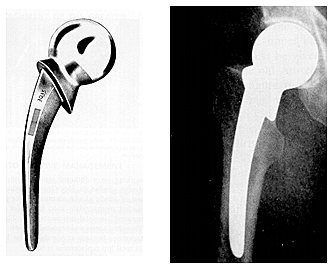

Después de evidenciar el desgaste del implante de los judet,El siguiente adelanto en el desarrollo de la artroplastia de cadera consistió en el diseño de endoprótesis metálicas con vástagos medulares para la fijación esquelética. Los dos modelos más populares fueron desarrollados en Estados Unidos por Fred Thompson en 1950 y A.T. Moore en 1952.

• VÁSTAGOS MAS LARGOS....

VÁSTAGOS MAS LARGOS....

permitían la transmisión de las fuerzas de soporte de peso a lo largo del eje del fémur, en lugar de generar fuerzas de presión a nivel del cuello femoral como ocurría en la prótesis acrílica de los hermanos Judet. Estos dispositivos que se basaban en la fijación a presión dentro del canal medular. La prótesis de Moore presentaba una fenestración en la parte superior del vástago femoral para permitir el crecimiento óseo en su interior aumentando así su fijación ósea.